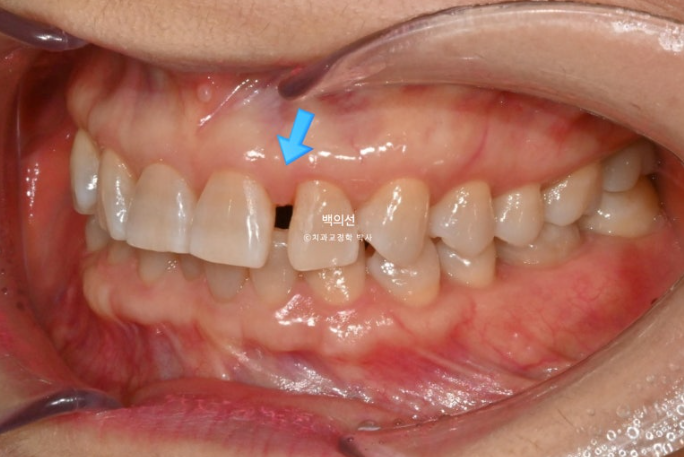

25.02

레진 치료를 감쪽같이 잘 해놓으셨습니다.

앞니의 뻗침이 있습니다.